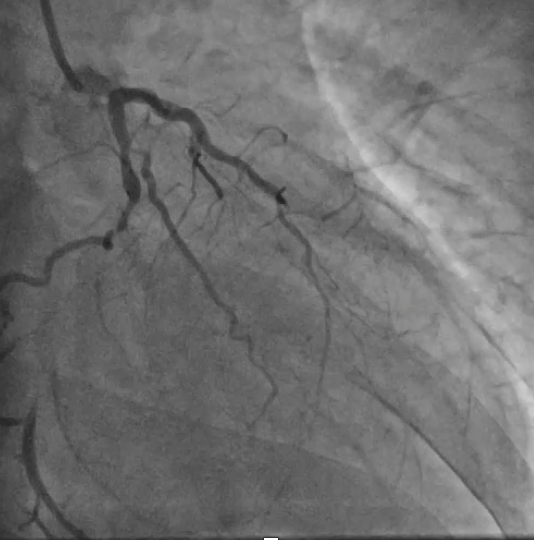

Coronary angiogram showed CTO in all 3 vessels. Impella assisted PCI was suggested in combined HEART team meeting in view of high surgical risk (STS score >8). Antegrade approach was adapted. LAD CTO was successfully crossed with Gaia Next 1 with Turnpike support. A 2.25x40mm stent was deployed to mid LAD and an overlapping 3.5x28mm stent was deployed to LM-LAD across wire protected LCx. Post dilatation was performed. Final IVUS and angiogram showed satisfactory result.

Upon removal of the workhorse wire from distal LAD, an unforeseen nightmare started. The wire tip entangled with the distal stent edge. Turnpike microcatheter was used to retrieve the stuck wire. Unfortunately, upon pullback, the wire fractured and only its proximal part was retrieved. The distal part remain stuck in the distal stent edge and uncoiled with filaments extending from stent edge into aorta. PingPong guiding was immediately set up. ClearStent showed distal stent edge deformity which rendered passage of any device including 1.0mm balloon impossible. In order to modify the obstructing stent struts at distal edge, it was decided to use rotablation. Direct wiring across the deformed distal stent edge with rota wire was successful. Pecking motion of rotablation was performed with the aim to clear the obstructing scaffolds. After 25 runs at high speed with 1.5bur, the deformed distal stent was successfully crossed. The trapped wire tip was unexpectedly released and fell into the septal branch. The fractured filaments were assessed with IVUS and ClearStent. Subsequently, the filaments were all retrieved with 2 twisting wires. IVUS confirmed complete clearance of any filament. The LM-LAD stent was again post dilated and optimized. Final angiogram and follow up restudy 4months later both showed satisfactory result with patent stents.